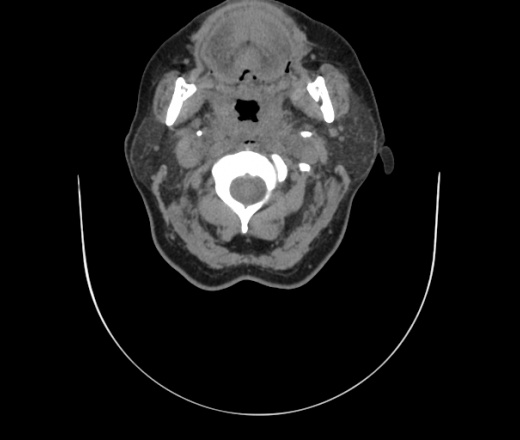

Женщина поступила в х/о спустя 4 дня после того как при употреблении карася подавилась костью.

Наличие газа в средостении на протяжении тел С2-С6 (медиастинальна эмфизема); рыбная кость на уровне тела С6.

При всем уважении, но говорить о медиастинальной эмфиземе, оценивая мягкие ткани шеи, как-то слишком резко. На мой взгляд, это ретрофарингеальное пространство.

Согласен с Вами; конечно, наличие газа в клетчатке ретрофарингеального пространства (затмение с опечаткой..). К сожалению, процесс "продвигается" к медиастиниту. Но почему никто, не отмечает наличие рыб. кости; или это для Всех очевидно?

Кость то мы сразу выявили, размеры где то 17*2мм, но ее так и не получается найти в этой каше